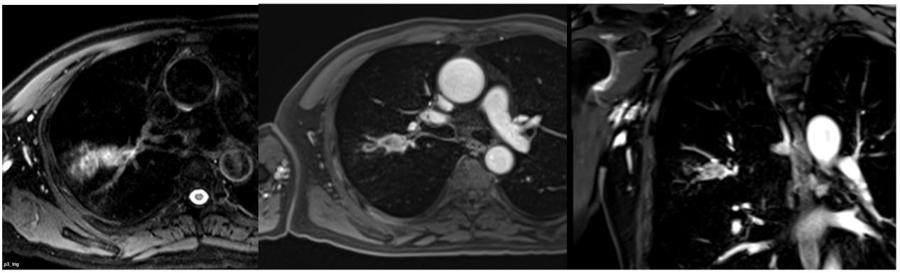

05高清功能成像平台

新的设备采用了全新的硬件系统,控制精度上比传统磁共振提高了若干数量级,图像的分辨率有了很大的改善,图像更高清,功能更强大,高清小视野图像在直肠和前列腺肿瘤分期具有重要意义。

胸部MRI,纵隔肿瘤无增强可以清楚显示病灶与血管分界。

胸部MRI,MRI对于最常见的肺结节显示能力以及对于肺内小结节的检出率已经大幅度提高。而且MRI比CT更容易鉴别肿块性质。